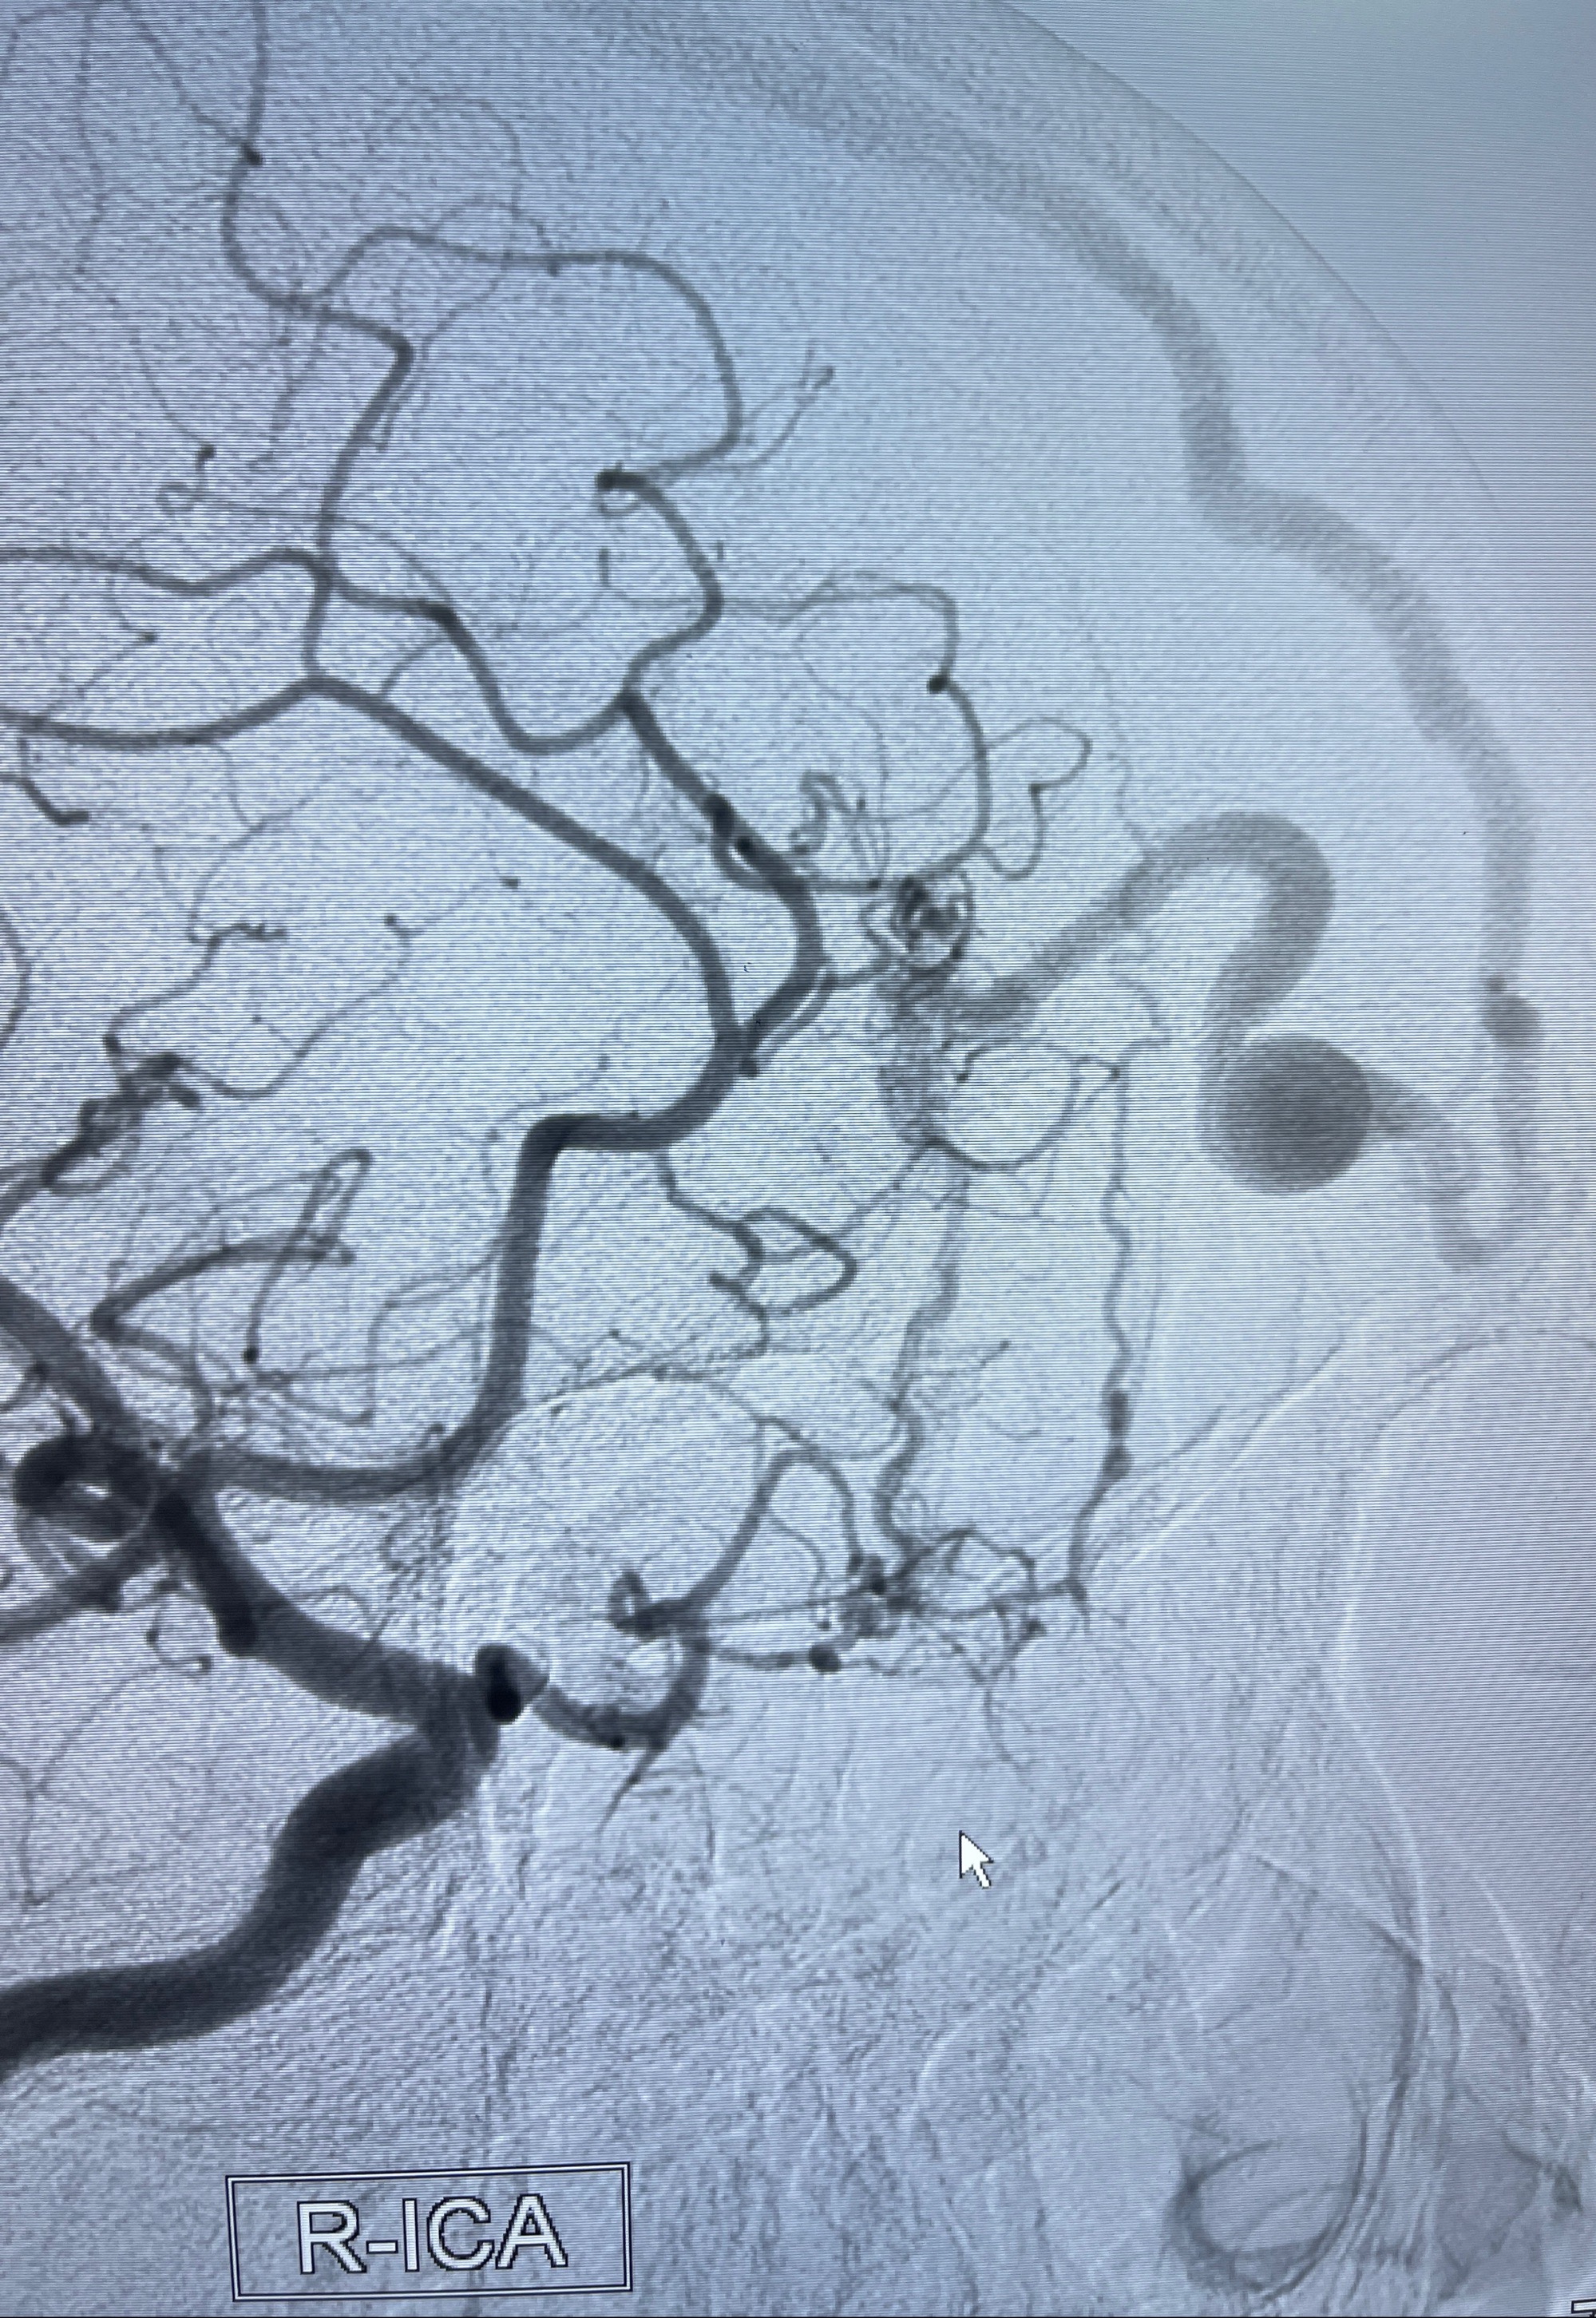

2023年8月21日]景德镇市第一人民医院脑血管造影检查,提示:主动脉弓、双侧颈总动脉、锁骨下动脉造影未见异常,左侧大脑前动脉静脉瘘。

2023-09-13全脑血管造影:前颅底硬脑膜动静脉瘘,供血动脉为双侧胼周动脉、眼动脉脑膜支,静脉向上矢状窦方向引流